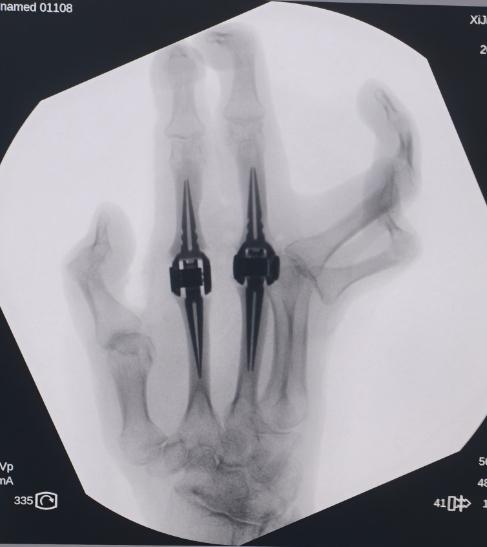

为了重拾对生活的信心和战胜疾病的决心,李女士对于手术治疗的愿望迫切,团队决定采用3D精准化设计+钛合金假体个体化诊疗方案,实施左手第2、3掌指关节同期置换术。

更为关键的是,团队借助3D模拟技术,提前演练手术全过程,通过微创小切口避开神经血管,精准去除病变软骨和增生滑膜,将假体稳稳嵌入掌骨与指骨…… 每一个步骤都经过反复推敲,确保术中操作零误差。“就像给手术画好了‘导航图’,每一刀、每一步都有精准依据。”主刀医生赵金康副教授介绍道。

手术如期开展,团队按照术前规划,以微创切口逐层分离组织,小心翼翼避开指神经和血管束,直达受损掌指关节处,精准剔除被炎症侵蚀的病变组织,清除致病 “元凶”。随后,将定制好的钛合金假体缓缓植入,关节柄稳固嵌入骨骼,关节头完美贴合软组织,整个过程如同 “精密的机械组装”,每一个流程都严格按照前期制定的设计参数实施。

手术的成功,不仅是李女士个人的“重生”,更是西京医院在风湿病内-外科综合诊治领域的重大突破。作为科室成立以来的第一例手指小关节置换手术,解决了类风湿关节炎手指置换中“假体个性化、植入精准化、术后稳定性”三大核心难题,为临床推广奠定了坚实基础。